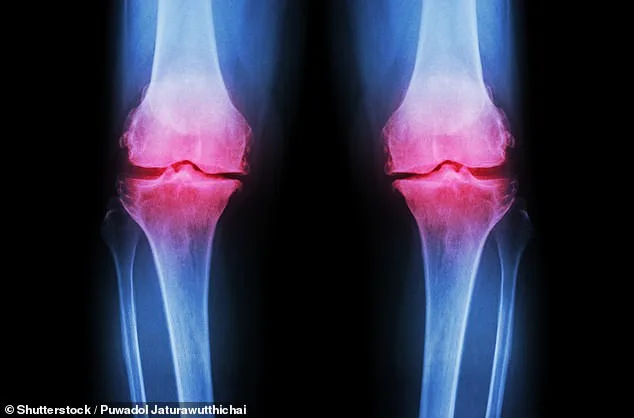

Groundbreaking new knee pain treatment for debilitating joint disease offers hope to 32 million Americans. Scientists at Columbia University have unveiled a revolutionary approach to treating osteoarthritis, a condition that affects nearly 32 million Americans, with 14 million specifically suffering from knee osteoarthritis. This degenerative disease, which erodes the cartilage cushioning joints, causes chronic pain, stiffness, and mobility loss, and currently has no cure. Existing treatments, such as physical therapy, corticosteroid injections, and full joint replacements, are either temporary or invasive. Now, researchers have developed a method to grow a living human knee in the lab, potentially offering a permanent solution. The process involves creating a 3D-printed scaffold made of biodegradable material, which is then seeded with bone and cartilage cells. Over the course of a year, these cells regenerate natural tissues while the scaffold dissolves, resulting in a fully functional lab-grown knee. Scientists believe this innovation could be transplanted into patients, restoring mobility and eliminating the need for traditional joint replacement surgeries.

Osteoarthritis, the most common form of arthritis, is becoming a global health crisis. Since 1990, the number of patients worldwide has surged by 132 percent, driven by an aging population, rising obesity rates, and disparities in access to care. Women and individuals from lower socioeconomic backgrounds are disproportionately affected, compounding the burden on healthcare systems and communities. As cases climb, the demand for effective treatments is growing—current options, such as painkillers and surgery, offer limited long-term solutions.